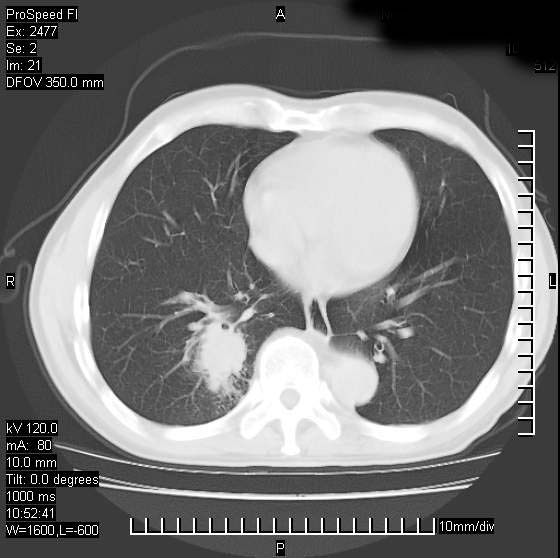

以下是引用天南地北在2007-10-9 14:29:00的发言:[br]1:右上肺结核[br]2:右肺下叶肿块:不支持肺癌,首先考虑炎性病变-肺脓疡可能性大[br]理由:1:临床病史支持,肺脓肿症状不明显应该是不规则服药造成。[br] 2:肿块边缘模糊,周围可见炎性渗出,长毛刺,内见支气管征,不过有点不规则。[br] 我感觉下肺癌这个诊断有点偏左,建议积极抗炎治疗后复查

以下是引用卜一在2007-10-9 15:55:00的发言:[br][br] [br] 1:右上肺结核[br]2:右肺下叶肿块:不支持肺癌,首先考虑炎性病变-肺脓疡可能性大[br]理由:1:临床病史支持,肺脓肿症状不明显应该是不规则服药造成。[br] 2:肿块边缘模糊,周围可见炎性渗出,长毛刺,内见空气支气管征,不过有点不规则。[br] 我感觉下肺癌这个诊断有点偏左,建议积极抗炎治疗后复查![br]支持! [br] [br] [br]

以下是引用wxy7406在2007-10-9 21:02:00的发言:[br]结合临床病史首先考虑感染性病变,但周围型肺癌不能除外,1.患者年龄偏大2.临床有咯血3.(也觉得是最重要的一点)病灶内有偏心性空洞。

以下是引用王仕学在2007-10-9 13:48:00的发言:[br]右下肺周围性肺癌可能性大,最好活检吧

以下是引用hhcckk在2007-10-9 15:18:00的发言:[br]右上肺病灶考虑结核,病灶多种形态并存(纤维化、增殖性病灶并存)[br]右下肺病灶比较难说,个人意见更趋向于“天南地北”的诊断----肺脓肿[br]1、病人有明显的寒战,高热,肿瘤病人很少出现[br]2、病灶周围的肺纹理走向柔和,没有肿瘤病灶常见的集束征[br]3、病灶边缘的毛刺较长,恶性肿瘤多为短毛刺[br]痰中血丝和病人的年龄是两个不利于良性肿块的因素,建议早点活检

以下是引用ydx_74在2007-10-9 15:53:00的发言:[br]右上肺结核,右下中心性肺癌可能大,肺门淋巴结肿大。